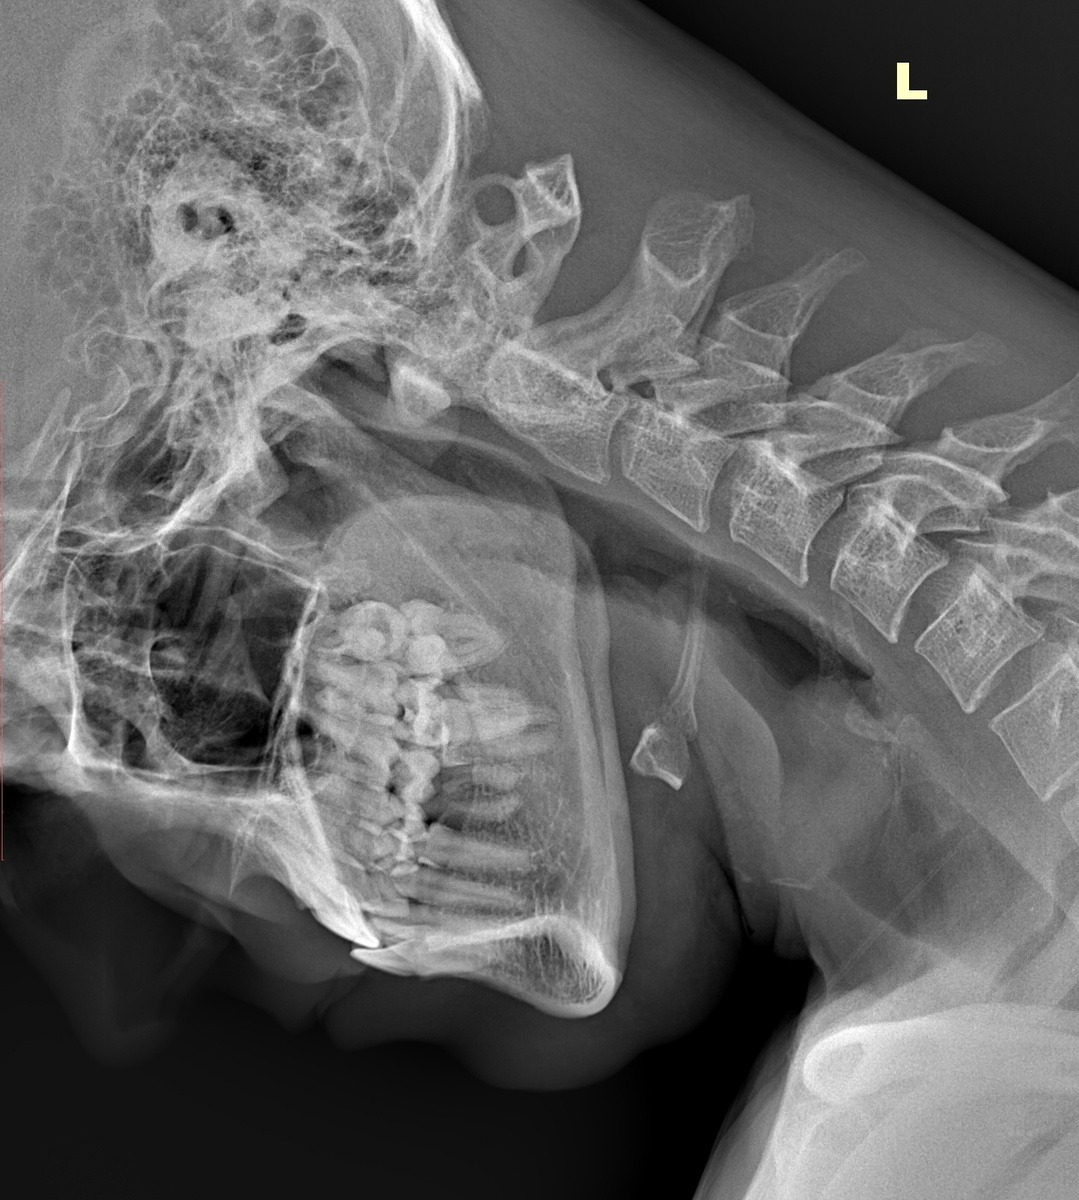

Аномалия Киммерли. Рентген - боковой снимок с согнутой шеей

Аномалия Киммерли. Рентген снимок в боковой проекции.